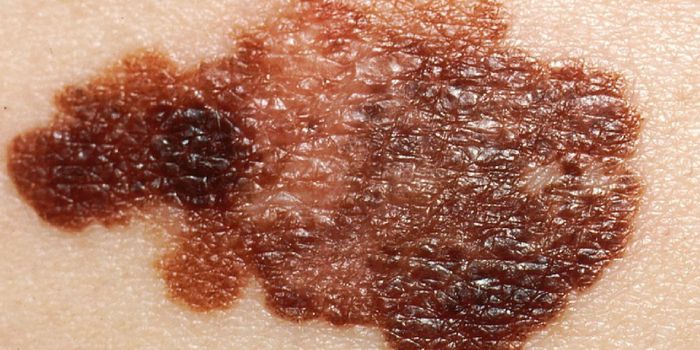

JUL 28, 2016CancerMetastatic melanoma is one of the most savage killers in its ability to escape detection and spread to other parts of th ...

AUG 30, 2017CancerThe next time you inspect your body for signs of skin cancer, pay special attention to new moles that were not there the ...